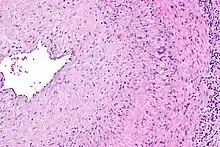

The gold standard for diagnosing temporal arteritis is biopsy, which involves removing a small part of the vessel under local anesthesia and examining it microscopically for giant cells infiltrating the tissue.[19] However, a negative result does not definitively rule out the diagnosis; since the blood vessels are involved in a patchy pattern, there may be unaffected areas on the vessel and the biopsy might have been taken from these parts. Unilateral biopsy of a 1.5–3 cm length is 85-90% sensitive (1 cm is the minimum).[20] A characterised as intimal hyperplasia and medial granulomatous inflammation with elastic lamina fragmentation with a CD 4+ predominant T cell infiltrate, currently biopsy is only considered confirmatory for the clinical diagnosis, or one of the diagnostic criteria.